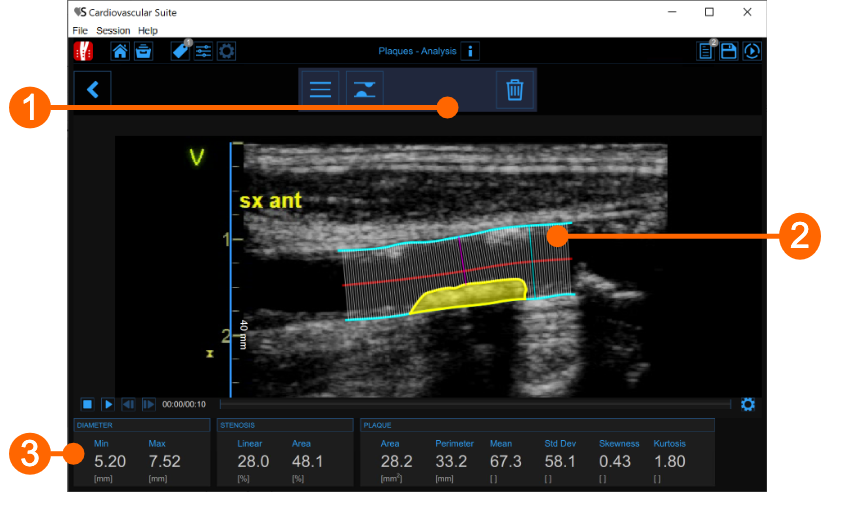

The plaque analysis window contains the following components:

- Setup panel

It contains the controls for tracing of the vessel borders, drawing a plaque and delete it. - Plaque analysis tool

After the plaque is drawn, the software automatically computes its area, perimeter, and the mean, standard deviation, skewness, and kurtosis of its grey level. - Data panel

This panel contains the computed values. In particular, it shows the minimum and maximum values of the diameter and the linear and circular values of the stenosis. In addition, if a plaque has been drawn, it also displays its area and perimeter, and the mean, standard deviation, skewness, and kurtosis value of its grey level.